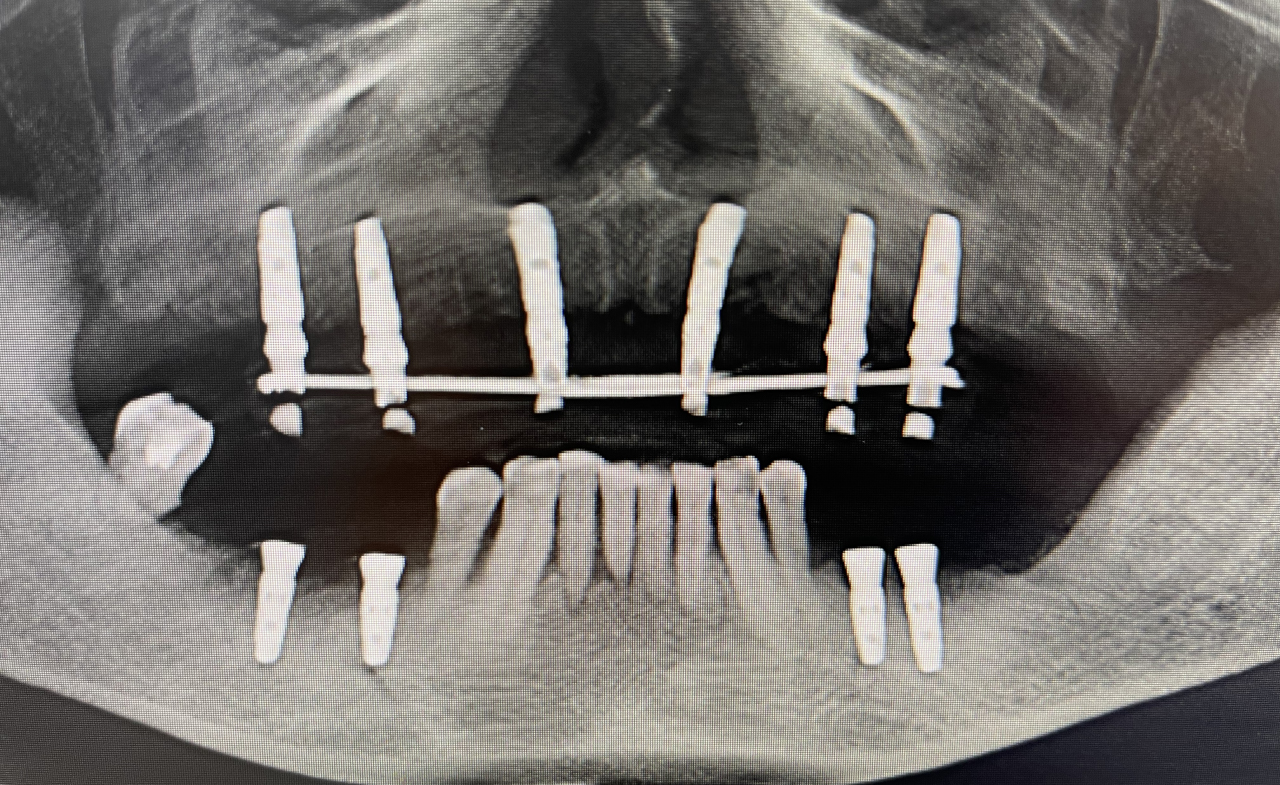

即刻修复3个月后:

上颌边缘骨稳定,行下颌后牙区种植,下颌植入4颗中科安齿种植体